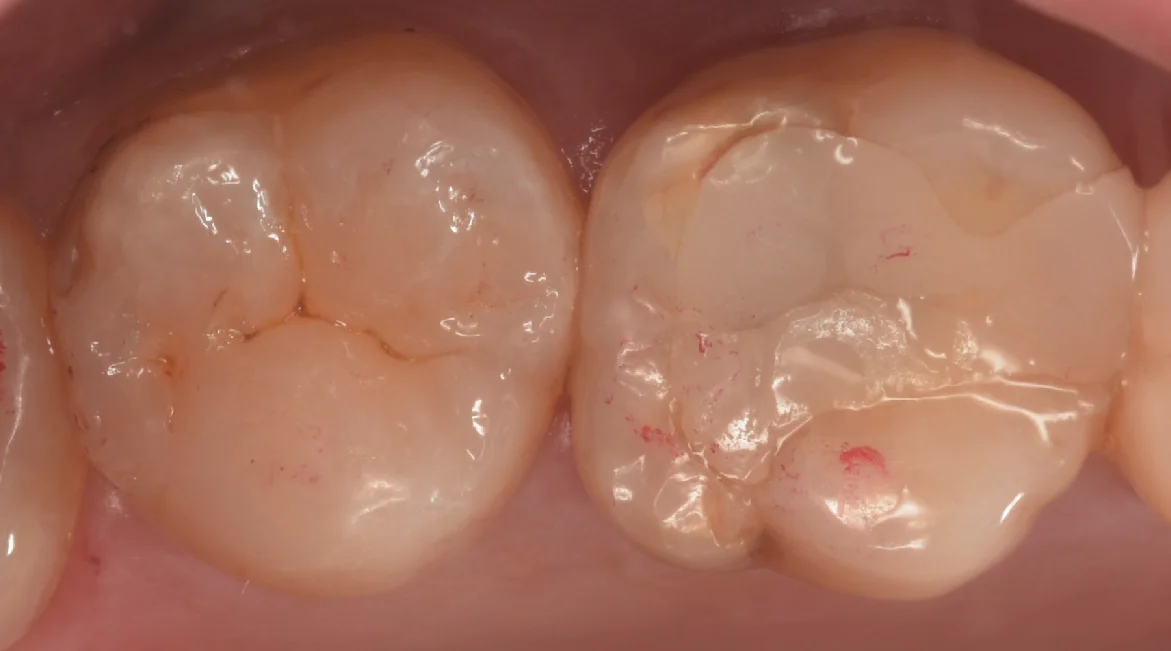

そして取り切ったのがこちらになります。

綺麗な歯の色が出たのがわかるかと思います。

状況としては個人的にはまだ1〜2年くらい様子見でも良かったような気もしますが、患者さんからの強い希望があったためこのまま介入することとなりました。

やるからにはきっちりやりたいので、なるべく歯の削除量を抑えた上でしっかりと虫歯を取り切りました。